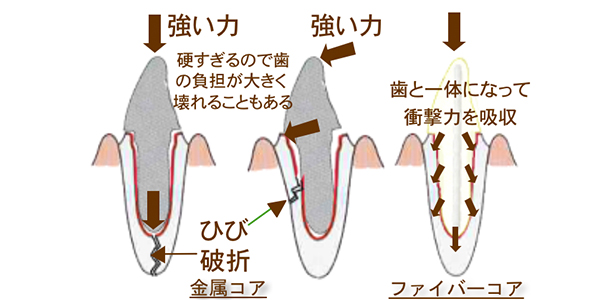

コア治療一覧

ファイバーコア:11,000円(税込)

| メタルコア | |||

|---|---|---|---|

| 審美性:× | 適合性:× | 耐久性:△ | 安全性:△ |

| ファイバーコア | |||

|---|---|---|---|

| 審美性:◎ | 適合性:◎ | 耐久性:◎ | 安全性:◎ |